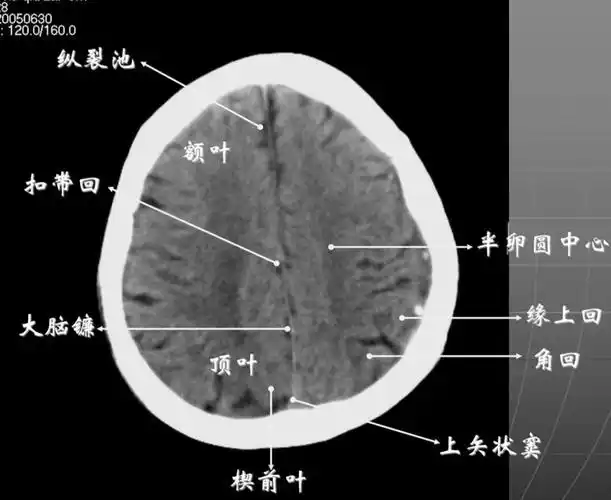

读懂头颅ct并不难教你成为读片小能手